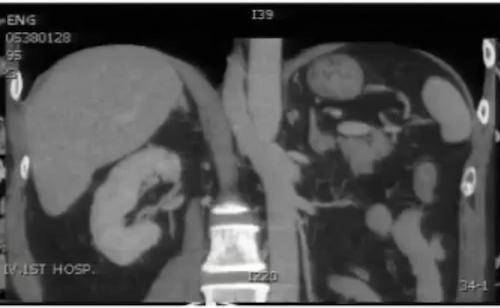

图2:冠状位重建显示下腔静脉肝段和肝下段缺如,向上直接延续为奇静脉

肾癌伴血管结构畸形

肾癌伴血管结构畸形患者的血管结构畸形往往容易被忽视。 在手术的过程中,如不注意就可能造成肝右叶血流的回流障碍,导致严重的临床后果。